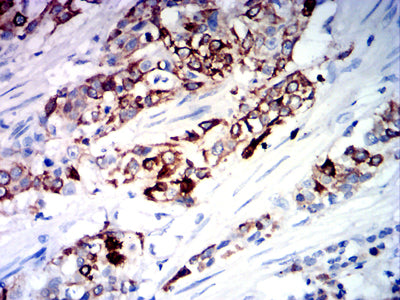

分类: 科研抗体货号: 32023别名: BIE; EHK; K10; KPP; BCIE; CK10应用: WB,IHC,IF,FCM反应种属: Human